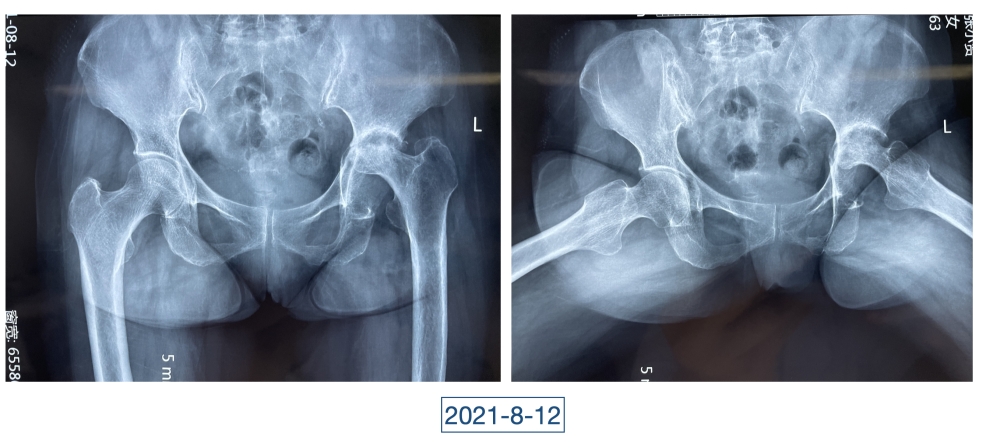

一直到了四月,因为髋关节疼痛的原因,她又来到红会医院关节病医院。李辉见到的黄大娘是坐着轮椅的,家里人说她已经到了卧床不起的地步,原本近107斤的人只用了3个月时间就瘦到了34斤。“这是患上了什么大病,才能让人变成这个样子?”看着憔悴不堪,可以用皮包骨头来形容的黄大娘,李辉心里一沉,担心起来。

全身上下11处骨关节被破坏!密密麻麻的诊断看得李辉毫无思绪,这么久都查不出来的病因能让他查出来吗?一时间,他也说不出话。看着黄大娘深深凹陷的双眼,浑身上下几乎看不见肉,就像罩着一层饥饿的青黄色的薄皮。过了好一会儿,他叹了口气,说:“先住下吧,用药把关节疼痛缓解一下,再想办法。”

近日随访得知黄大娘身体好转,李辉脸上的笑容掩饰不住,他说,据查阅文献,11处感染灶,这是全世界感染灶最多的骨关节感染,但现在,这罕见、复杂的病已经被治愈。